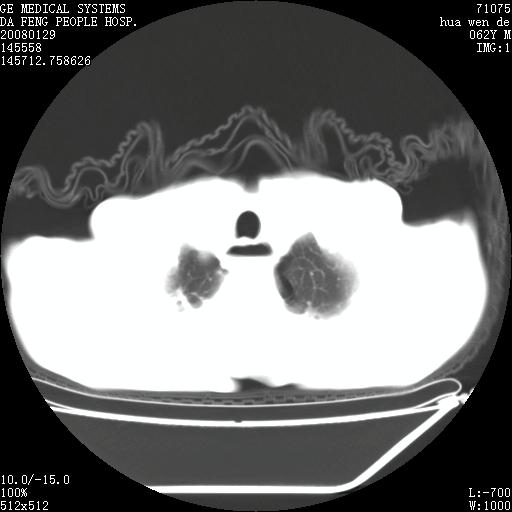

男性,67岁。作肺部检查时发现

1.整个食管扩张,未见明显占位性病变,贲门区亦未见明显占位病变,考虑:贲门失驰缓症;

2.右上肺病变边缘可见毛刺,囊壁厚度不均匀,周围境界较清楚,未见炎性渗出性影,右上肺外带可见片状影,边缘不清,考虑:肺癌伴空洞形成、右上肺炎。

食管全程扩张,壁均匀不厚,喷门失弛缓症

右上肺空洞可见液平,临近肺野磨玻璃密度,考虑1.结核2.脓肿

贲门失驰缓症.肺部感染伴脓肿形成。支持!是否吸入性要结合临床诊断,我们影像是看不出来的。但胸腔胃能排除(1.没有手术史支持,2.双侧胸廓对称,胸壁、肋骨及胸膜规整,3,食管壁明显扩张内壁光滑,胸腔胃黏膜皱襞多较厚)。

右上肺空洞可见液平,临近肺野磨玻璃密度,考虑1.结核2.脓肿 支持!